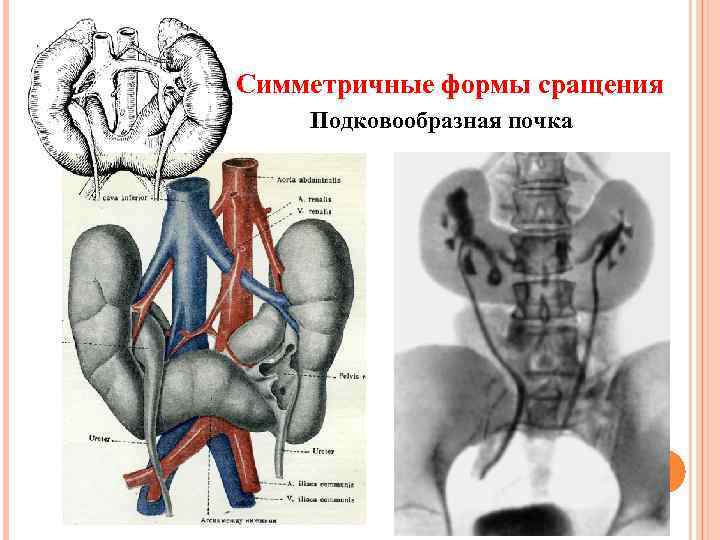

Симметричные формы сращения Подковообразная почка

Симметричные формы сращения Подковообразная почка